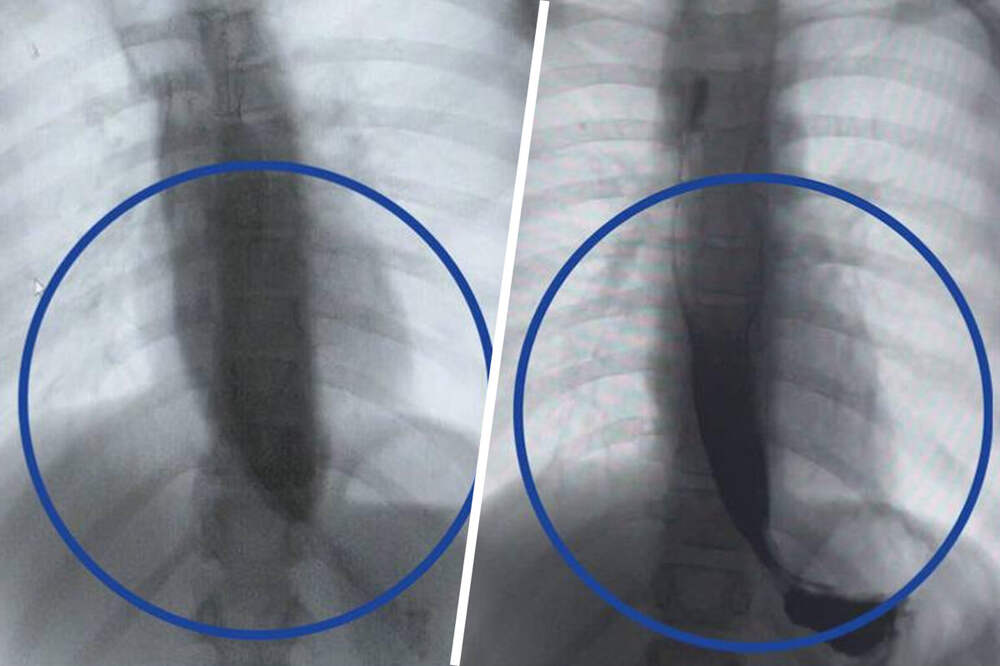

Врачи Детского клинического центра им. Л.М. Рошаля спасли девятилетнюю девочку с редким заболеванием - ахалазией кардии, из-за которого ее пищевод был расширен в пять раз. Об этом сообщили в пресс-службе минздрава Московской области.

Медики рассказали, что пищевод пациентки из-за патологии был

...Далее